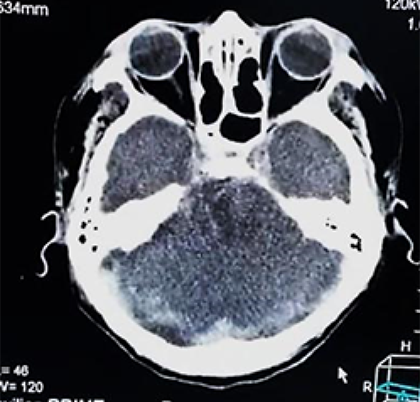

La evolución posterior se caracterizó por permanecer estable hemodinamicamente, con mejor control de la presión arterial, sin deterioro neurológico, bajo terapia de reemplazo renal; sin embargo al sexto día, en forma súbita presenta mayor deterioro neurológico con un Glasgow de 9-10/15 y mala mecánica ventilatoria, rápidamente se intuba a la paciente para protección de vía aérea, asociado a analgo-sedación; se optimizan las medidas de protección cerebral y se realiza un control tomográfico (Figura 3 a, b).